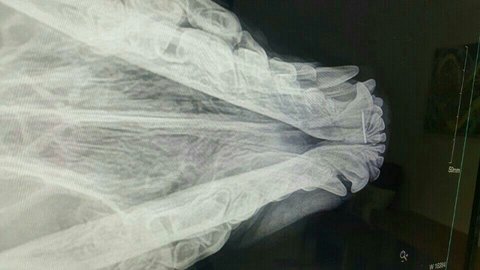

차를 돌려 2차선에 누워있는 아이를 조심히 갓길로 옮기고 상태를 보니 앞다리 하나가 덜렁거리고 입에 출혈이 나고 있었습니다.

다급히 병원으로 옮겨 검사결과 앞다리 골절과 턱에 금이간 상태였습니다.